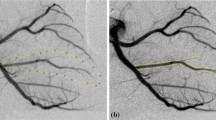

Coronary arterial volume (V) was determined using angiographic images acquired during end-diastole after contrast material has propagated throughout the epicardial arteries, but before the opacification of the coronary sinus and termination of power injection. A calibration of the imaging chain for quantifying iodine mass from X-ray densitometric signal was performed by acquiring an image of the calibration phantom over the pig hearts [10, 23, 24]. The calibration phantom was placed on the chest so that its projection overlapped the heart. Correction was made for differential magnification of the phantom and the heart. Power injection of contrast material was assumed to momentarily replace blood with contrast material. The known iodine concentration in the contrast material and a linear regression analysis between measured gray levels and known iodine masses in the calibration phantom were used to convert gray level to volume. A region-of-interest (ROI) was drawn around visible arteries for volume quantification (see Fig. 2). Coronary arterial volume was then calculated using densitometry. Gray values were converted to volume measurements with a conversion factor determined from the acquired image of the calibration phantom [19].

Coronary blood flow (Q S) was determined from the change in volume within one cardiac cycle. A global ROI encompassing the visible arteries, as well as the microcirculatory blush, was drawn for flow measurement (see Fig. 3). Coronary flow was then quantified using a first pass distribution analysis. The first pass distribution analysis assumes that contrast material of a known concentration enters a collection reservoir via a single arterial input and that all measurements are made prior to the contrast material leaving the selected region designated by the ROI. The change in the measured densitometric signal was converted to volume measurement using system iodine calibration. The time period of the cardiac cycle was calculated from the image acquisition rate of 30 frames/s. The ratio of the measured volume change to the time period of the cardiac cycle yields volumetric coronary blood flow [10, 11, 22].